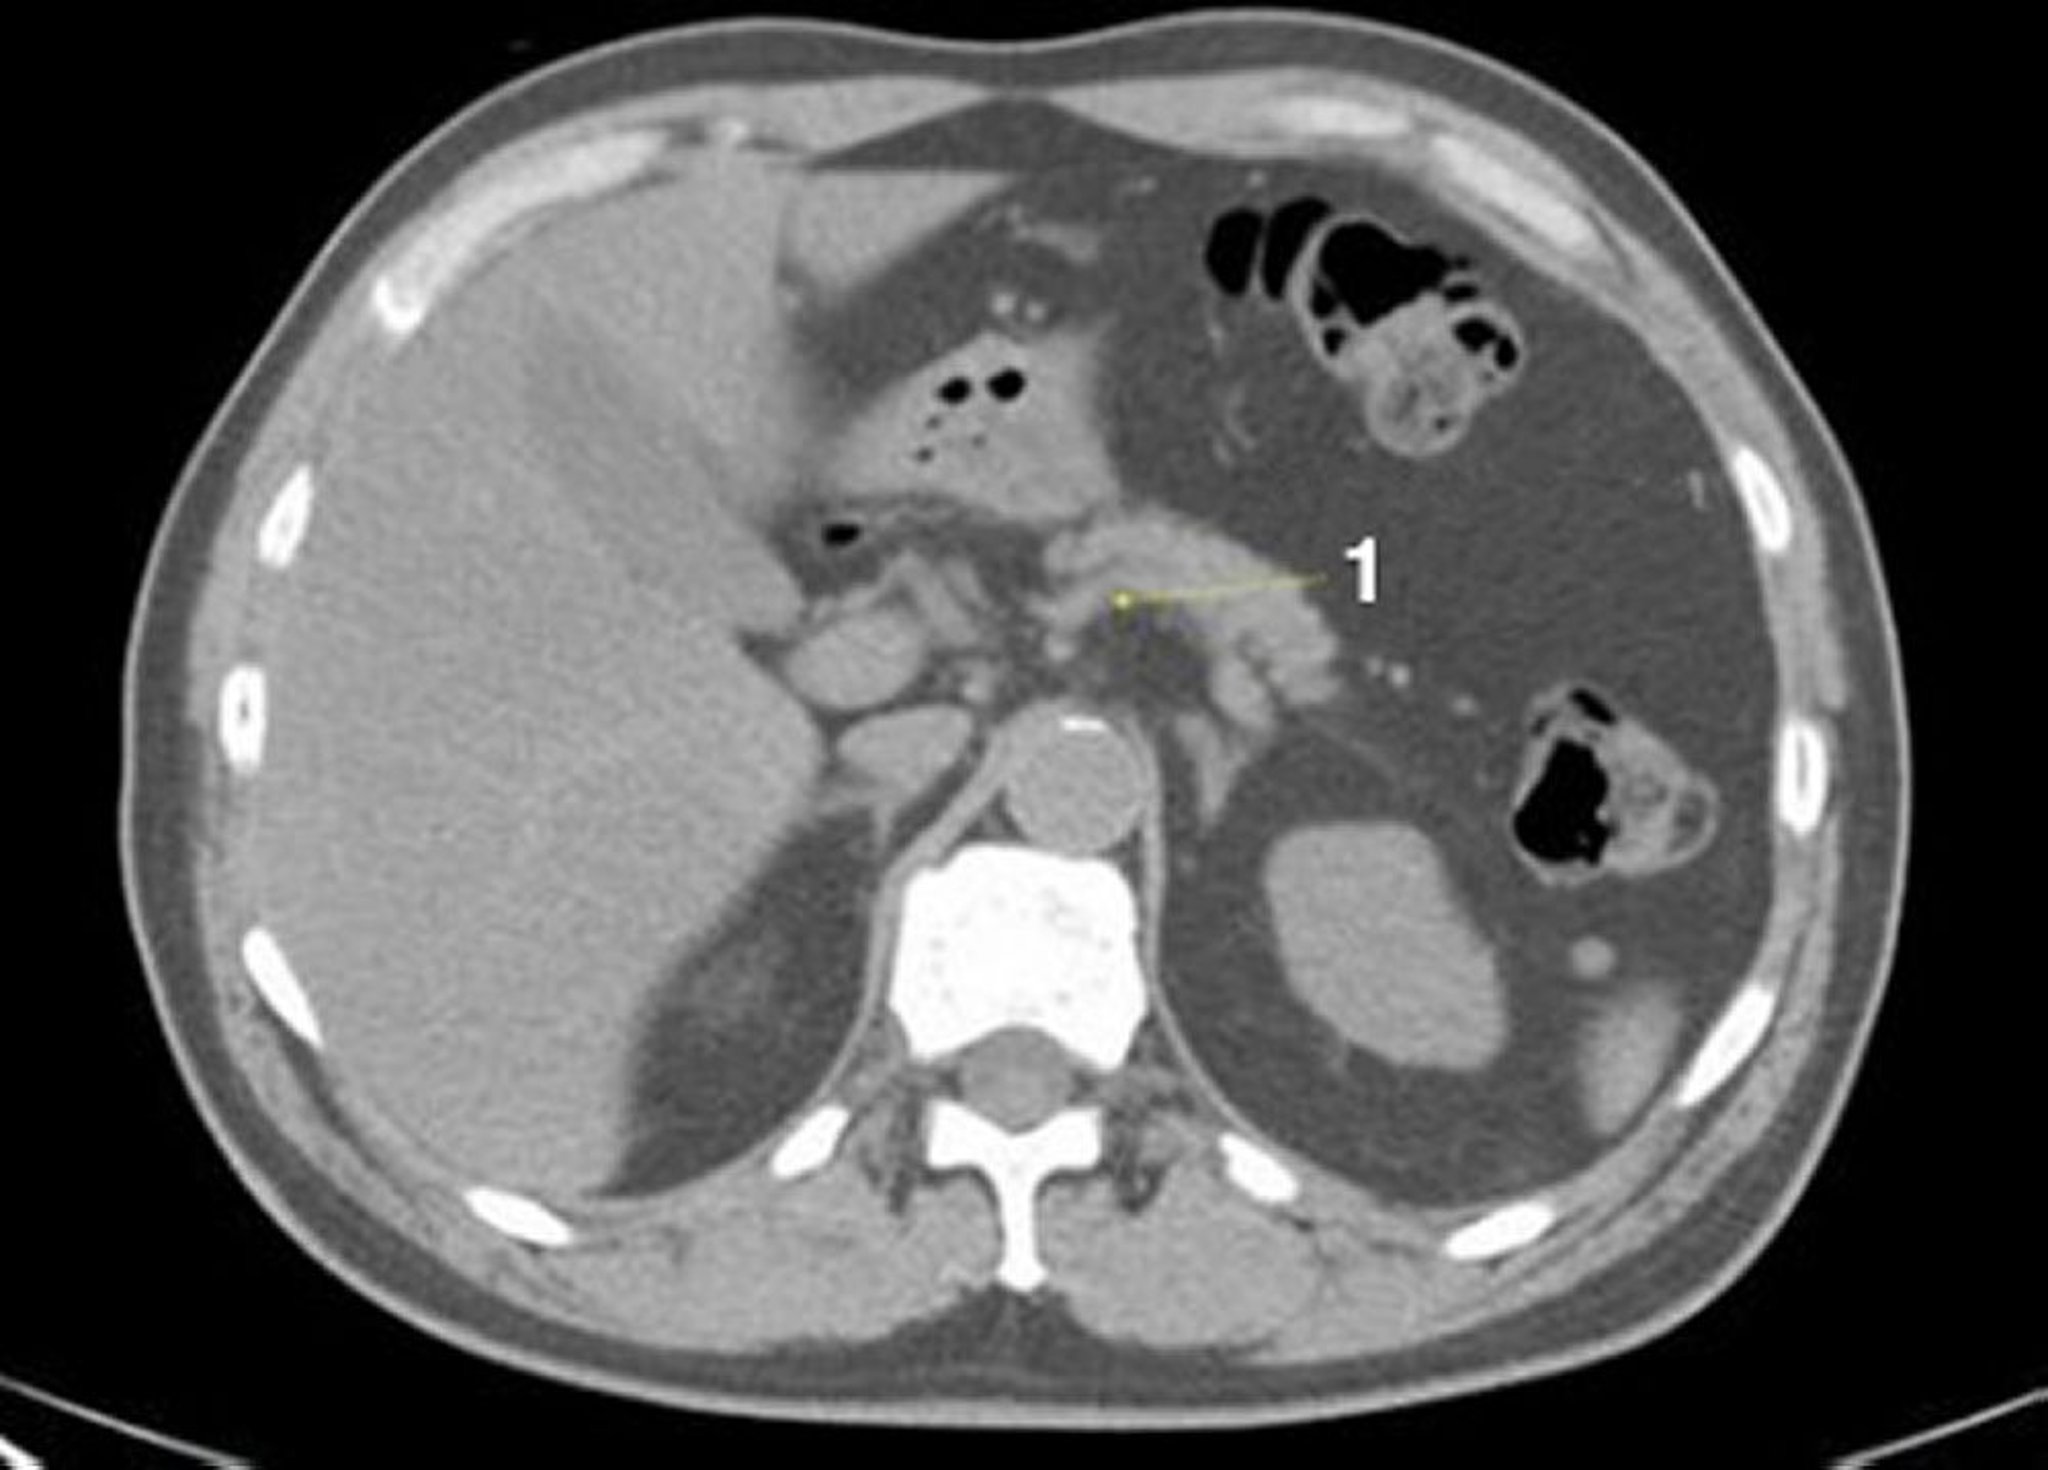

TDM sans contraste de l'abdomen et du bassin montrant une anatomie normale (diapositive 7)

1 = veine splénique.